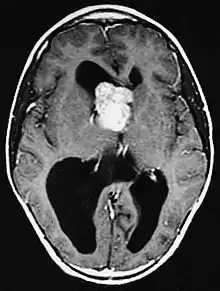

Diagnosis is made by imaging with a contrast-enhanced MRI or CT scan of the brain.